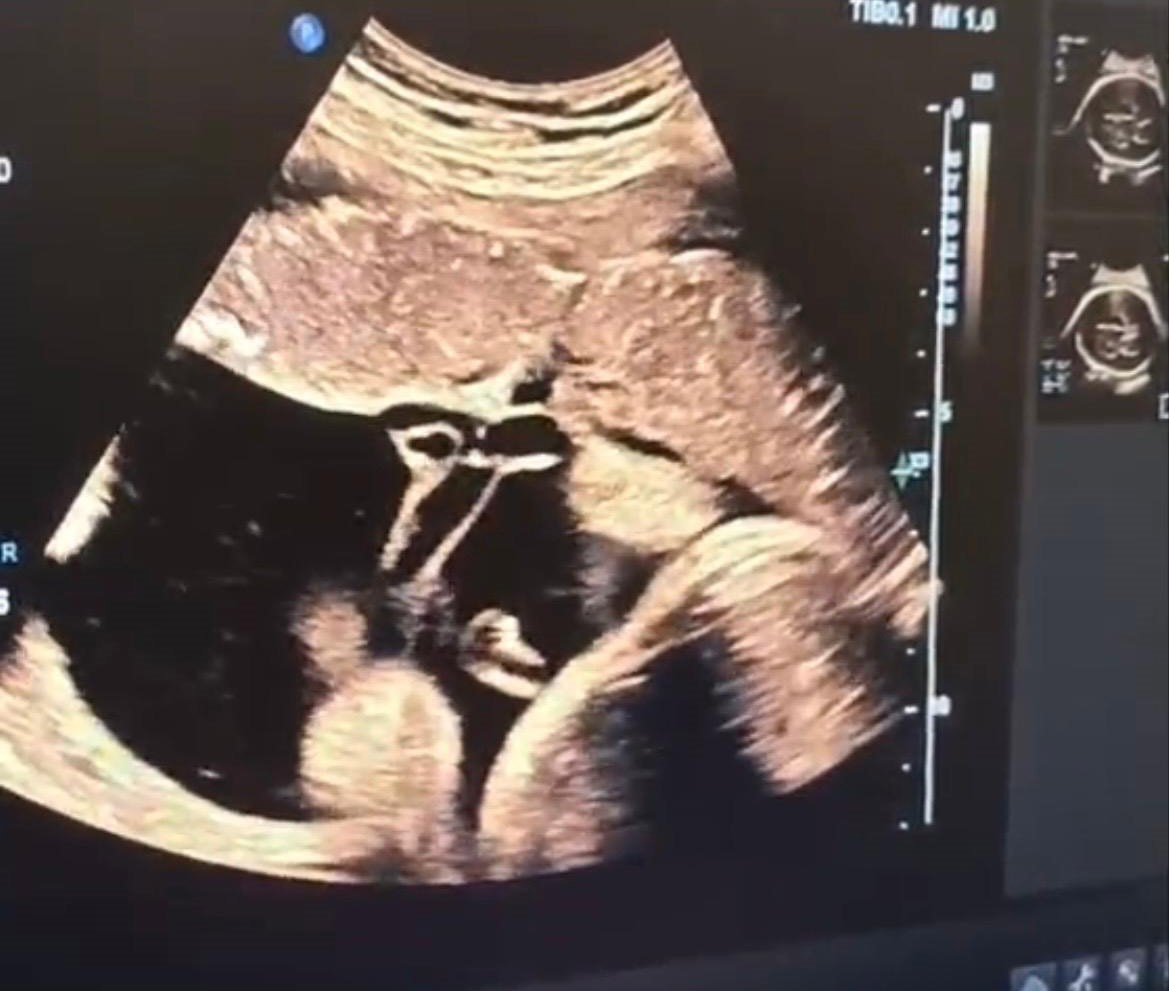

Halk arasında "anne karnında kan nakli" olarak bilinen intrauterin fetal kan transfüzyonu, bebekte ciddi kansızlık (anemi) tespit edilmesi halinde uygulanan hayati bir tedavi yöntemi olarak biliniyor. İşlem, ultrason eşliğinde anne karnından ince bir iğne yardımıyla bebeğin göbek kordonuna girilerek gerçekleştiriliyor. Önce bebeğin kan değerleri ölçülüyor, ardından eksik olan miktar kontrollü şekilde naklediliyor. Lokal anestezi altında ve steril şartlarda yapılan müdahale yaklaşık 30-45 dakika sürüyor.